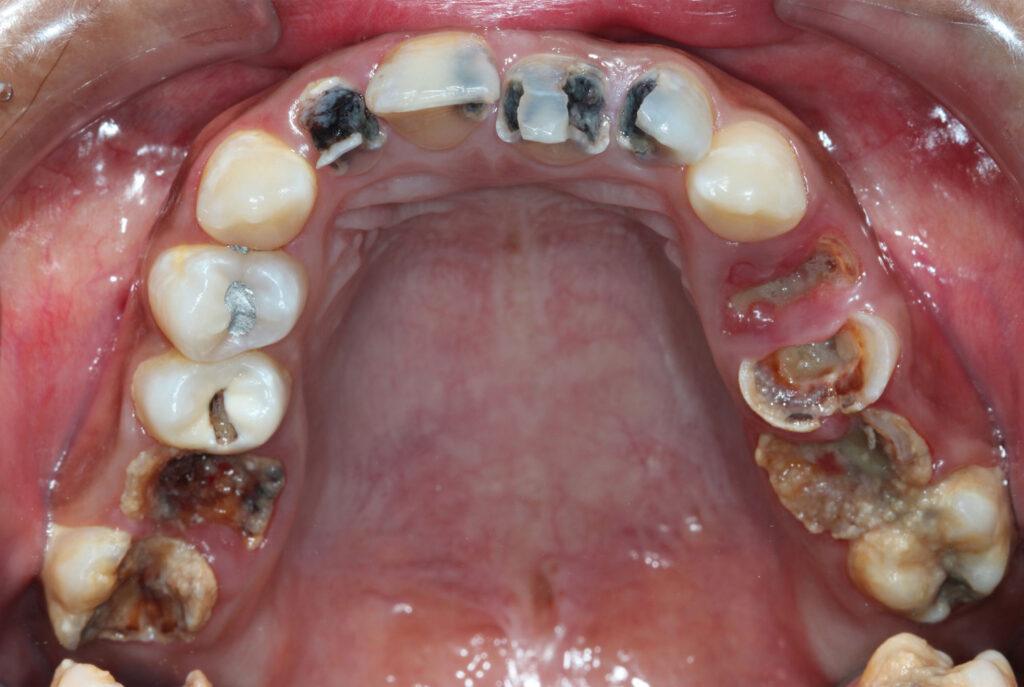

Common Dental Emergencies

Unexplainable Toothache

Toothaches are not just a painful nuisance or something you should take lightly. They are your body’s way of telling you that something is not right in your mouth. When you experience sudden and unexplainable tooth pain, find a qualified emergency dentist to help diagnose and treat the issue.

Swollen or Bleeding Gums

Although occasional gum irritation is not a dental emergency, gums that won’t stop bleeding, especially if accompanied by pain and swelling, can indicate an underlying dental or health issue.

It is not normal to experience bleeding gums without any obvious cause. See your dentist right away if you’re experiencing these symptoms.

Abscessed Tooth

A dental abscess is a severe and potentially life-threatening condition in which a pocket of pus in the tooth has led to an infection. A tooth abscess may cause:

• Fever

• Sensitivity to hot and cold

• Persistent toothache

• Tender lymph nodes in your neck

• Swelling in the face

• A pimple-like bump on your gums near the infected tooth

This condition is an emergency as the infection can spread into your jaw, surrounding tissue, and other areas of the body.